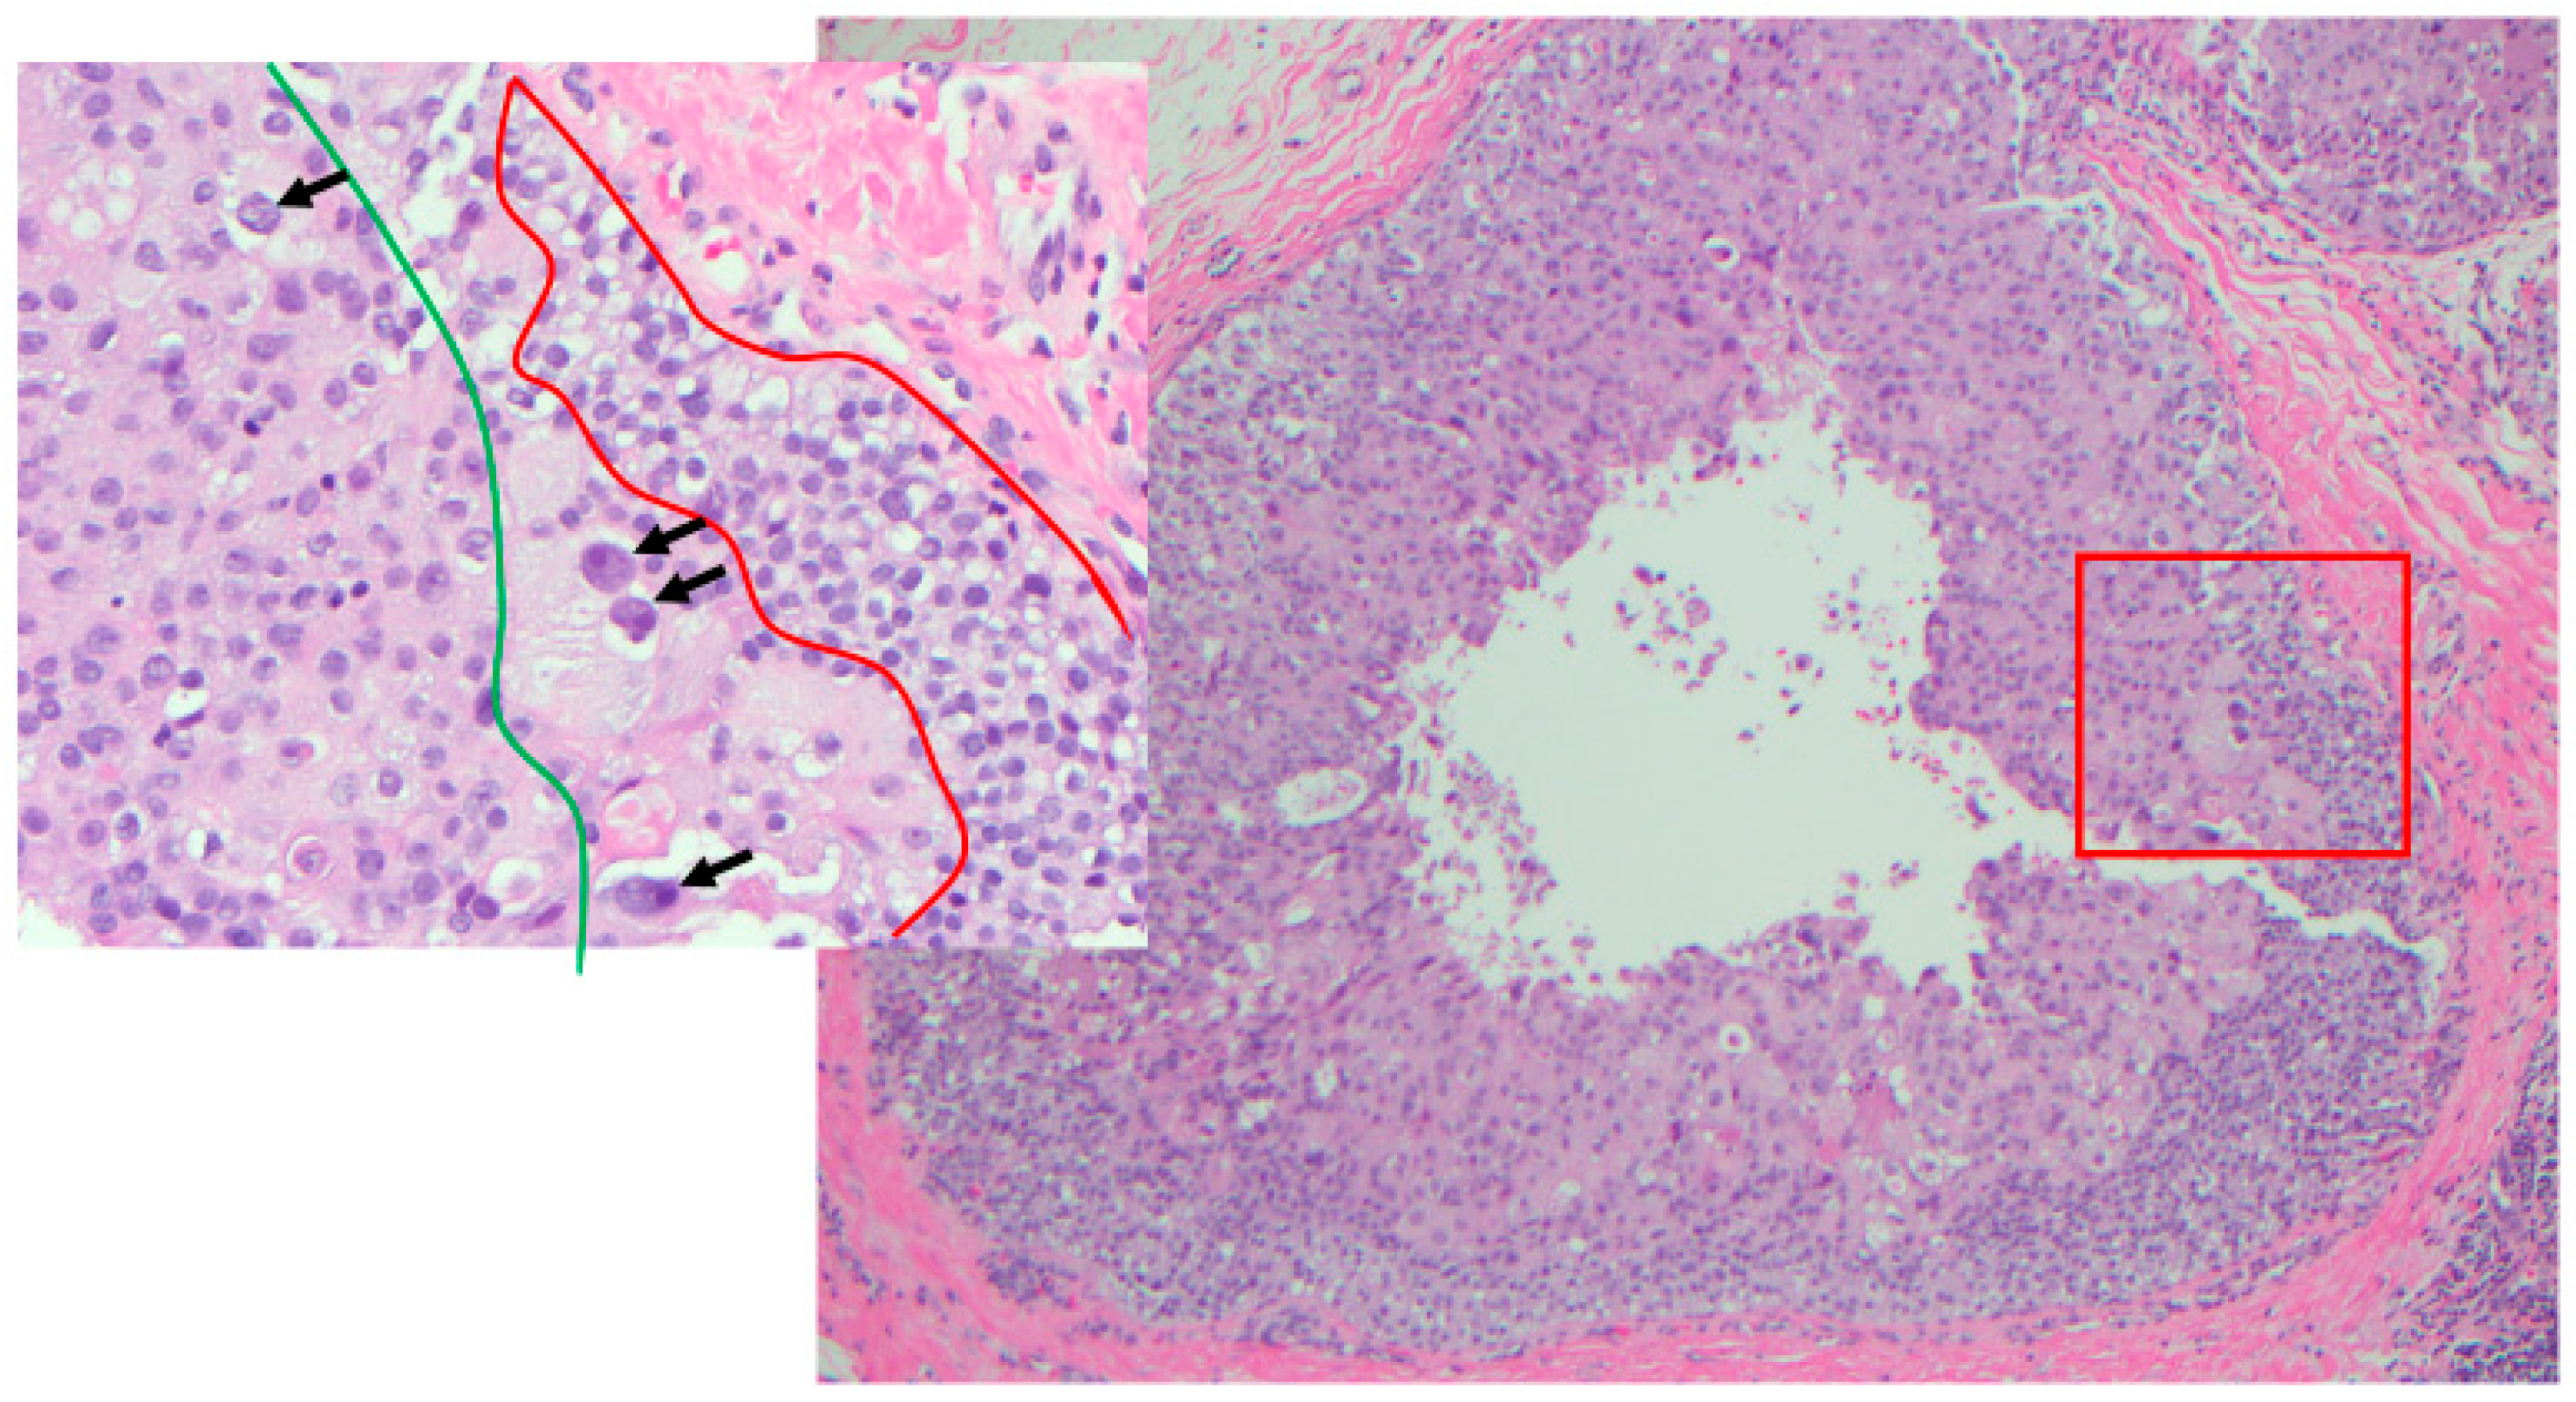

Figure 7.

Heterogeneity of nuclear grade within the same duct (H&E 10×); in box LG (within red zone), IG (with green zone) and HG (arrows) (H&E 40×).